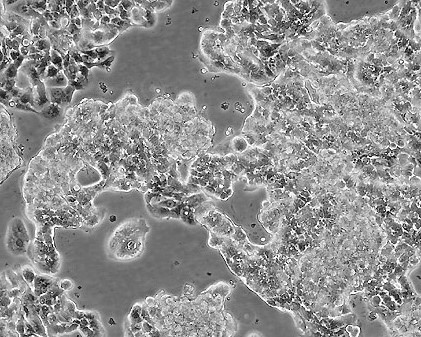

Ca Ski

90%RPMI-1640+10% FBS

Temperature: 37°C ; Carbon dioxide (CO₂), 5%

贴壁细胞